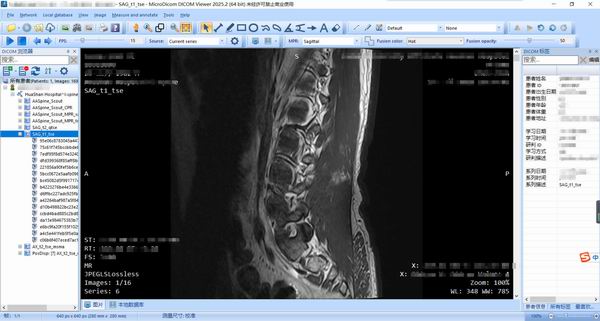

[下载]一款免费看DCM格式医疗影像的软件——MicroDicom

二、MicroDicom软件

MicroDicom是一款专业且功能强大的医学图像浏览工具。MicroDicom官方版能够帮助医学工作者轻松的浏览各种dcm格式的医学图像,包括RLE、JPEG、JPEG2000等格式。MicroDicom软件还支持将dcm转换为常见的jpg、bmp等图像格式

官网下载(WinX64_v2025.2.8154_ZIP)

2.汉化补丁

蓝奏云盘(提取码:52pj)

3.安装方法

a.直接解压ZIP包

b,将汉化补丁mDicom.exe覆盖到源程序中

c.首次打开软件后,选择中间的:保证不作为商用,就可以用了。